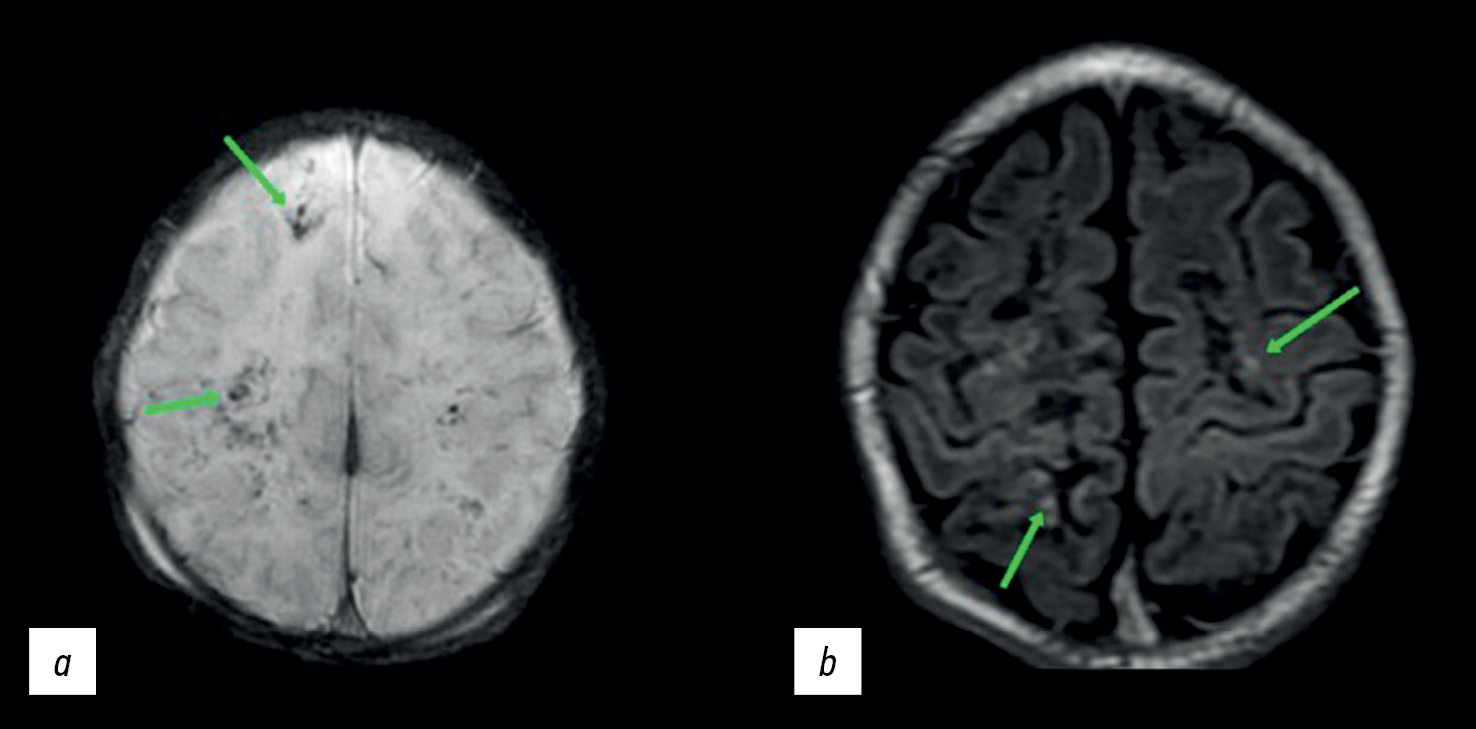

Among the numerous lesions in the presented instance, the brain MRI revealed single regions with hemorrhagic features compatible with ischemia (Figure 3а). This suggests that not all ischemia foci were accompanied by bleeding. Although necrotic areas eventually turn into encephalomalacia areas, some areas with minimal damage may recover entirely and even be consistent with the normal structure of brain matter in MRI [16]. The hyperintense signal was seen in the cortical area and at the gray/white matter interface in the frontal and parietal lobes in T1-weighted images (T1-WI) (Figure 3b). These areas resemble cortical necrosis, which occurs after ischemia damage to the cortex, resulting in monocyte infiltration and phagocytosis of cell fragments in the damaged structures. T1 images are hyperintense due to deposits of denatured protein of the dead cells and/or lipid-loaded macrophages [17].

Fig. 3. Magnetic resonance imaging (MRI) of the brain: (a) susceptibility-weighted images (the arrows show microhemorrhages) and (b) Т1-weighted images (the arrows indicate hyperintense areas of the cortical necrosis).